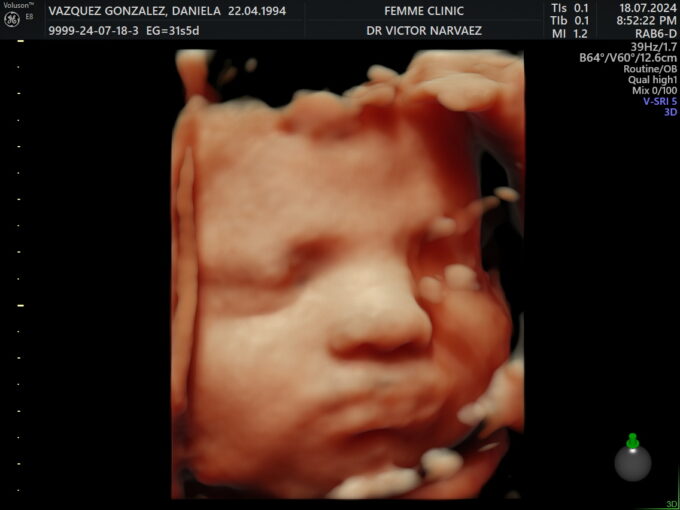

Mi embarazo fue profundamente deseado, cuidado y consciente. Viví cada semana con respeto y atención, sabiendo que ese pequeño latido era el sueño de muchos años. Hubo momentos de miedo, como un sangrado en el segundo mes, pero también una certeza muy fuerte: estaba haciendo todo lo posible por proteger ese milagro. Por eso decidí guardar silencio casi hasta el final, cuidando ese proceso con todo mi corazón.

Julia Elena nació por cesárea, después de un embarazo intenso y lleno de emociones. Escuchar su llanto, verla por primera vez y reconocer en su carita algo de su papá y algo de mí fue indescriptible. Incluso cargándola, besándola y mirándola, me costaba creer que por fin estaba ahí.